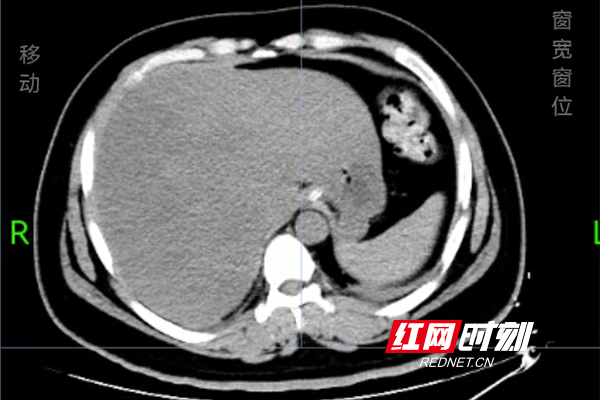

治疗后,肝脏血管内积气消失。